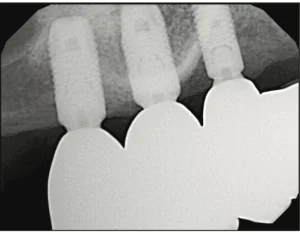

INTRODUCTION When restoring adjacent implants in the partially edentulous patient, the decision on whether or not to splint them is a common clinical question. Although